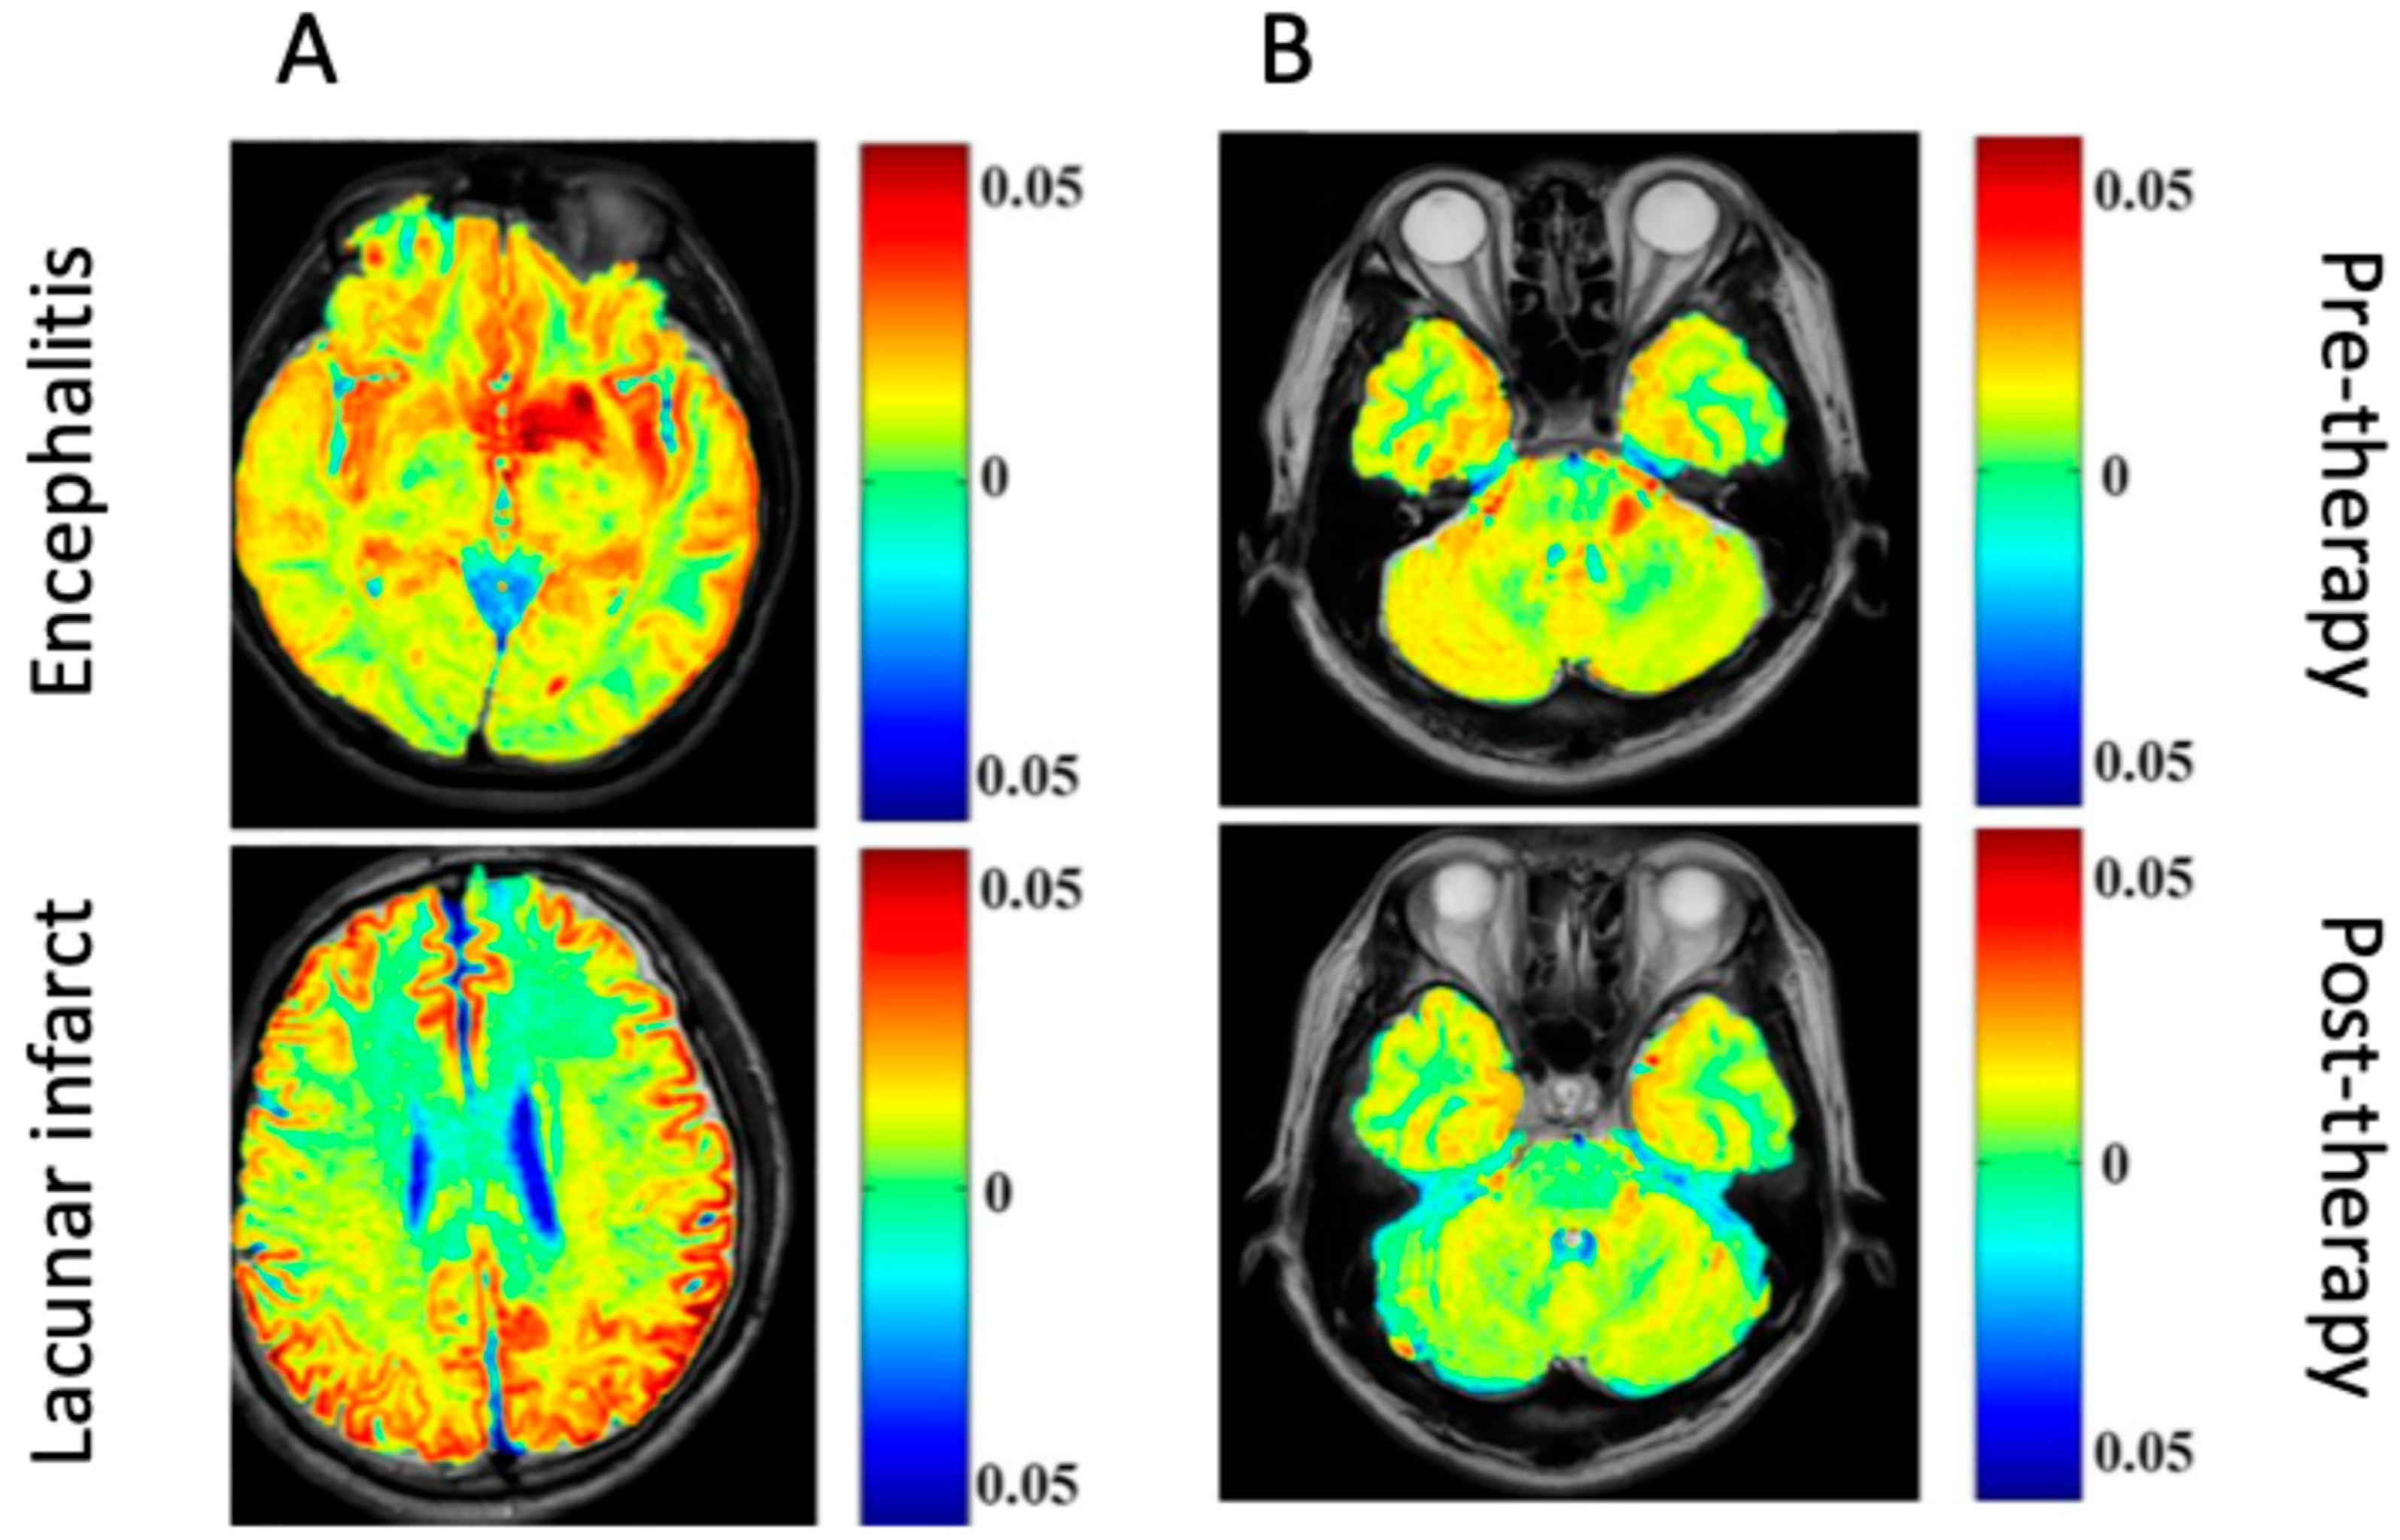

In particular, CEST has significant diagnostic potential in differentiating infective pathogenesis in the CNS from other lesions (e.g., ischemic, neoplastic). The bacCEST study [45] was able to differentiate brain abscesses and tumors, which is currently unreliable with conventional MRI techniques. Still, a statistically significant difference between the abscess and tumor signal was recorded using different B1 values (1 μT and 3 μT for brain abscess and tumor, respectively. This relationship was preserved when tested with two different tumor models in rats (specimens were injected with F98 or 9 L glioma cell lines). The gluCEST signal has also successfully distinguished between encephalitis and ischemic lesions, where glutamate concentrations are found to be decreased in lacunar infarction regions but increased in encephalitis lesions [46].

A few studies have been published regarding diagnostic investigation using gluCEST to image the destruction of the blood–brain barrier by brain abscess in SD rat specimens [4]. This preliminary study showed that gluCEST may diagnose abscesses more reliably and at a higher resolution than MRS [4]. Another study explored the use of gluCEST imaging in vivo in rats and humans to diagnose encephalitis [46]. In model rats, glutamate concentrations were significantly associated with the inflammation caused by S. aureus-induced encephalitis lesions; furthermore, the gluCEST signal increased throughout the infection. This suggests that further studies could investigate how changes in glutamate concentrations could be used to monitor encephalitis development throughout the infection [46]. Another study used gluCEST imaging to examine the detection of early changes occurring in sepsis-associated encephalopathy (SAE), a severe systemic infection complication affecting the CNS [47]. Unlike the use of conventional MRI, combining gluCEST with diffusion kurtosis imaging (DKI) could detect early abnormalities in diseased rat cohorts [47]. Lastly, another group investigated the glutamate signal changes during SAE within the hippocampus in SD rats using gluCEST [48]. In this study, H1-MRS imaging was used to understand if CEST could provide high spatial resolution for quantitative brain mapping and lesion visualization in SAE. The results found that gluCEST imaging could provide sensitive data regarding changes in glutamate in the hippocampus of the rats with SAE with comparable quality to H1-MRS imaging [48].

CEST MRI can also be used to visualize the infections of the CNS over time, essentially monitoring their status and providing information on prognosis and therapeutic efficacy. In rat models, bacCEST can monitor antibiotic therapy response in brain abscesses. This visualization method was also superior to structural MRI, as the bacCEST contrast showed a change much earlier than T2WI (after 4 days instead of 10 days) (shown in Figure 2 as an illustration) [45]. Another preclinical study investigated the effects of N-acetylcysteine (NAC) treatment on SAE in SD rats [47]. The gluCEST signal was significantly higher in the SAE group than in the NAC-treated group or the controls, and the CEST distribution also differed in the SAE group. These findings suggest that the effects of treatment on the cortex could be visualized through gluCEST imaging in this disease process.

The severity of lesions in encephalitis can also be tracked over time with gluCEST during intravenous immunoglobulin therapy. The gluCEST signal in encephalitis lesion areas was significantly decreased from pre- to post-treatment in human participants, which correlated with the signal intensity changes visualized on conventional MRI imaging [46]. However, the gluCEST signal change was specific to encephalitis lesions; lacunar infarction lesions treated with the same therapy could not be adequately visualized over time with gluCEST [46].

Generally, differences in the imaging between different events in the brain could provide a wrong diagnosis. For example, the difference between encephalitis and lacunar infarction could not provide a differential picture for an accurate diagnosis. However, a clinical study demonstrated an increase in the gluCEST signal in patients with encephalitis compared to a decreased gluCEST signal in patients with lacunar infarction [46]. To validate their finding, patients with encephalitis were treated with a cocktail of immunoglobulins, which caused a decrease in the encephalitis lesions (1.34% to 5%) (Figure 2).

Figure 2. Glutamate chemical exchange saturation transfer (gluCEST) in patients. (A) Differential images comparing encephalitis and lacunar infarct. (B) Images showing encephalitis before and after immunoglobulin therapy [46] (Images obtained from an open-access article distributed under the terms of the Creative Commons Attribution License (CC BY)).